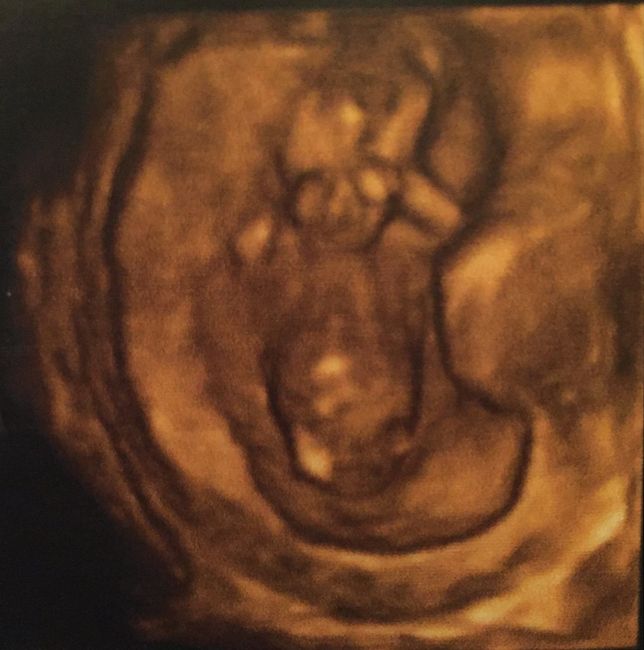

Il nostro/a piccolo/a sta bene siamo felicissimi anche se durante la tn é stato davvero poco collaborativo si é perfino grattato le chiappe in diretta.. : vi lascio qualche fotina e il vs piccolo quanto era lungo alla 13esima sett?